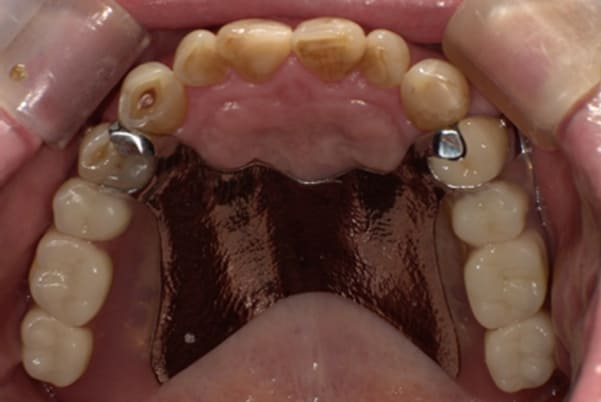

症例レポート[CASE.02]

入れ歯がカパカパして痛い、

歯がぐらぐらする

- 男性(60代)

- 入れ歯がカパカパする、歯がぐらぐらして痛い、食いしばれない

- 上顎精密総金属床総入れ歯

- 下顎精密金属床部分入れ歯

上の前歯が重度歯周病により動揺し、残せない状態のため、入れ歯も動揺がありました。

ご自身の歯に負担の少ないバネ、また見た目も改善

バネをかける歯は繋げることで強度を増し、歯への負担を軽減し、歯の寿命を長くする設計へ。

バネがかかる歯の被せ物は、歯への負担を減らし、入れ歯が動きにくいようになる形態をあらかじめ付与することで、より入れ歯の機能が高まります。

治療を行う際、被せ物や入れ歯は、別々に考えるのではなく、一口腔単位としてお口全体のことを考え最良の治療計画を立てることが歯の寿命、機能効果を向上させるため、専門医としてこのことは常に心掛けて治療を行っています。